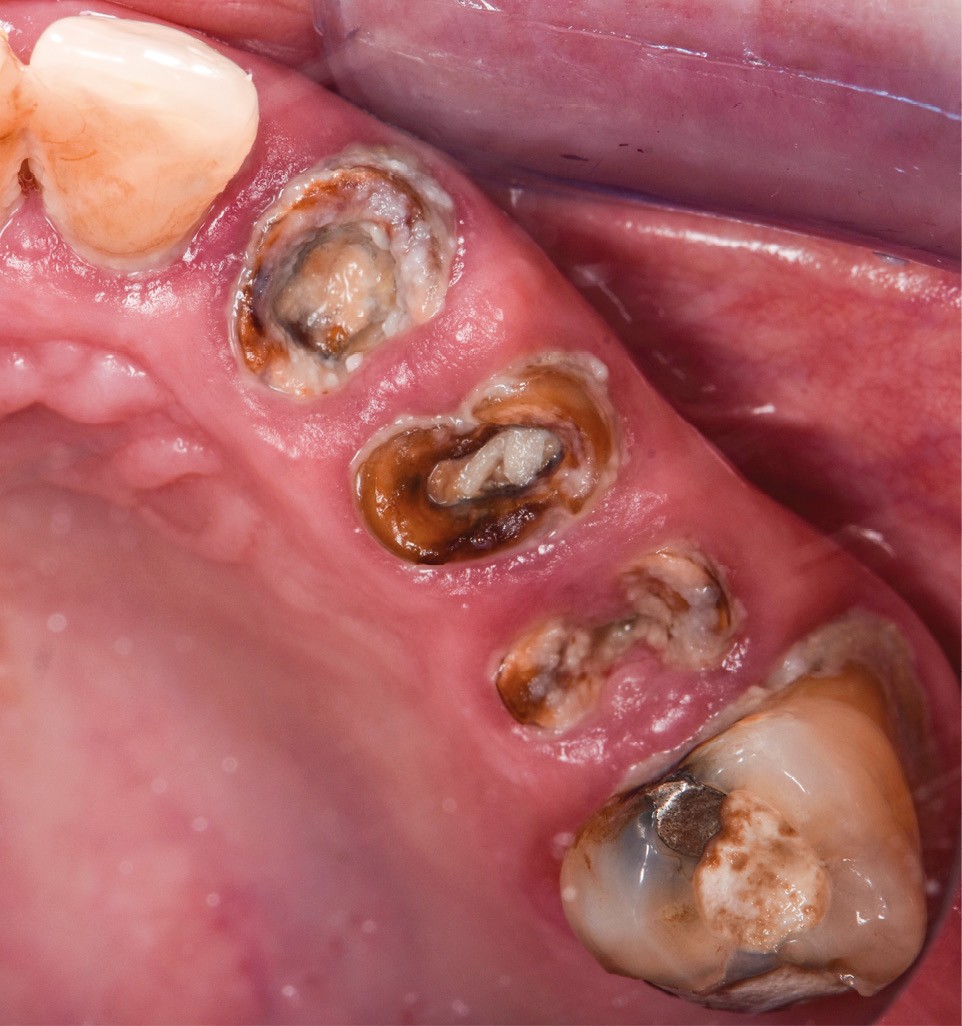

Une patiente de 41 ans se présente en urgence pour le descellement de couronnes solidarisées 23/24/25. À l’examen clinique, on note des piliers dentaires avec une faible hauteur coronaire, des lésions carieuses et une préparation intracanalaire invasive (fig. 1a-b). La 26 présente une mobilité de type 3, une égression, une exposition de la furcation et, après examen radiologique, une importante et ancienne perforation du plancher pulpaire. Radiologiquement, les traitements endodontiques sont insuffisants (fig. 2) et les dents 24/25 présentent une image apicale radio-claire.